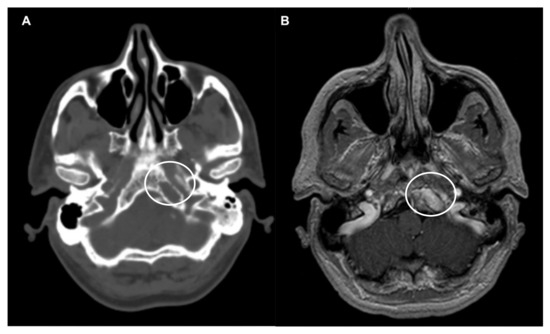

Secondary tumors of the CVJ are primarily plasmacytomas and metastases. Plasmacytomas of the CVJ region are monoclonal plasma cell neoplasms that arise from the nasopharyngeal submucosal tissue (extramedullary plasmacytoma) or the marrow space of the clivus or cervical vertebrae (solitary plasmacytoma of bone) (Figure 2). Plasmacytomas show a homogeneous signal intensity on T1- and T2-weighted MR images [66]. Breast carcinoma is the most common primary site of metastasis in the CVJ, and it is reported to be the site for one third of all cases [67]. Other primary tumors include thyroid, lung, renal and prostate carcinomas. The signal intensity and enhancement pattern on MR images may reflect the cell type of the original malignancy and may be associated with necrosis or hemorrhages [21].

Figure 2.

Lower clivus solitary plasmacytoma. (A) Axial CT scan showing a lytic expansile lesion at the left lower clivus (circle). (B) Axial T1-weighted after contrast injection image showing a heterogenous and hyperintense lesion (circle). A minimally invasive endoscopic endonasal biopsy disclosed the plasmacytoma.